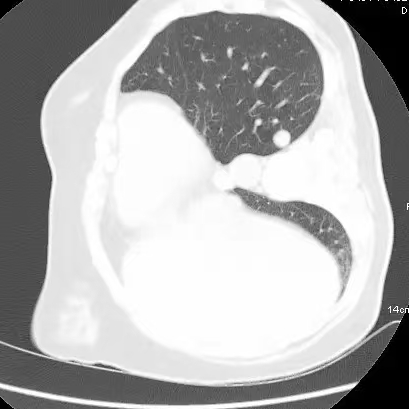

健康直通车: 健康是生命的宝贵财富,也是幸福生活的基石。为了更好地服务广大百姓,传播健康知识,葫芦岛市第二人民医院推出“健康直通车”专题栏目,将专业的医学知识以通俗易懂的方式传递给每一位市民,掌握科学的疾病预防方法,共同构筑健康中国的坚实基石。 什么是肺结节 肺结节是指肺内直径小于或等于3cm的类圆形或不规则形病灶,影像学表现为密度增高的阴影。大于3cm的称肿块。肺结节依其密度不同可分为实性结节、部分实性结节、磨玻璃结节,其中部分实性结节的恶性可能性最大,磨玻璃结节次之,实性结节尤其是小的实性结节结节最可能是良性的。 肺结节的常见病因 1、良性(约90%) 🔸 感染:结核、真菌、细菌性肺炎后遗留的瘢痕; 🔸 非感染:错构瘤(良性肿瘤)、炎性假瘤、血管瘤等。 2、恶性(约10%) 🔸原发性肺癌(如腺癌、鳞癌); 🔸转移性肿瘤(其他器官癌症转移至肺)。 如何根据影像判断肺结节性质 1、依据结节大小判断 🔸小于0.5cm的肺结节绝大多数都是良性的,属于微小结节。即使部分小于0.5cm肺结节是恶性的,但是适当的观察不影响预后。每年复查一次胸部CT就可以。 🔸大于0.5cm持续存在的纯磨玻璃结节,观察6个月,若持续存在,不管有无进展均多数是恶性的,视患者意愿,手术可以立即做也可观察至进展再做,不影响预后。 🔸大于0.8cm的部分实性结节恶性可能性非常大,应积极评估结节边缘毛刺、分叶、胸膜凹陷等征象。 🔸若实性部分大于0.5cm,恶性率显著提高。若在3~6个月随访期间实性部分增大或者总体部分增大,都可以考虑手术切除。而即使小于0.8cm的部分实性结节也需3个月就复查对比。 2、依据肺结节形态 如CT上提示病灶形态不规则、毛刺、分叶、胸膜凹陷、空泡征、血管集束征等,符合恶性肿瘤的征象。 🔸结节与正常肺组织之间界限非常清楚的恶性可能性大。 🔸结节密度不均呈混杂密度或均匀较大纯磨玻璃结节也基本是恶性的。 🔸有胸膜牵拉(不管是肺表面的脏层胸膜还是叶间裂部位的胸膜)的恶性可能性大。 🔸结节有浅分叶、细毛刺,密度较高而与周围肺组织边界不清的恶性可能性大。 🔸磨玻璃或混合磨玻璃结节存在小空洞的恶性可能性大。 🔸影像上似慢性炎表现,而没有炎症相关的其他异常,特别当所谓炎症区域内部或一侧与正常肺组织之间界限非常清楚的基本上是恶性的。 3、从结节发展情况来看 所有随访中增大进展的都需要考虑恶性可能,不进展而持续存在的纯磨玻璃结节也需考虑恶性。 葫芦岛市第二人民医院肺结节诊治中心孙振教授深耕肺结节领域四十余载,凭借对临床实践的执着钻研与深厚积淀,在肺结节精准诊断及鉴别诊断领域形成独到见解。他系统总结海量临床病例,创新性提炼出一套科学化、规范化的肺结节全周期诊疗体系,尤其在早期微小结节的影像特征识别、良恶性风险分层等方面积累了丰富经验,为众多患者提供了精准、高效的诊疗方案。 人民医院·人民名医 孙振 主任医师 三级教授 ·葫芦岛市第二人民医院胸外科主任、肺结节诊治中心主任 ·中国医科大学客座教授 ·原央企总医院著名胸外科专家 ·辽宁省医学会胸外科委员 ·辽宁省抗癌协会肺癌专业委员会委员 ·辽宁省细胞生物学学会食管癌专业委员会理事 ·主持多项科研成果获科技成果奖、科技进步奖、国家专科奖项 医学成就 从事胸外科临床工作近40年,担任胸外科首席专家及科室主任20余年,是我省胸外科领军人物,推动肺癌、食管癌等胸部肿瘤外科的规范化诊疗,在央企总医院牵头成立了肺结节诊疗中心,率先开展CT引导下肺内小结节定位切除,既确切完整切除肺内小结节,又降低肺功能损害。 专业特色 擅长肺癌、食管癌的外科手术和综合治疗,在各类高难度胸外伤手术治疗、胸腔镜微创手术、胸腺瘤手术及复杂并发症处理方面具有高深造诣,尤其擅长肺癌早期诊断,胸部小结节CT早期肺癌的鉴别等。完成各类高难度胸外科手术5000余例,其中微创手术占比达90%,治愈率达98%,多项业务填补省内空白。 开展的高难手术 胸腔镜肺部结节微创手术、肺癌根治术、食管癌根治术、各种纵隔肿瘤切除术、胸骨后甲状腺手术及胸部复合性外伤的抢救手术等。